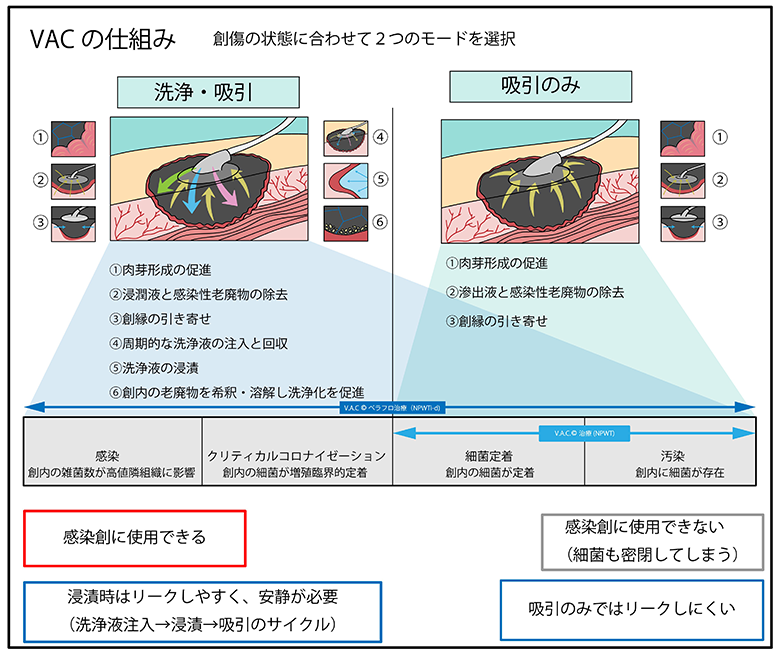

皮膚潰瘍につける治療器械 局所陰圧閉鎖療法 日本医科大学武蔵小杉病院。

褥瘡と難治性潰瘍についてとその治療法について横浜市立大学附属病院。

創内持続陰圧洗浄療法と局所陰圧閉鎖療法を用いて下肢を救済し得た壊死性筋膜炎の1例 Leg salvage in necrotizingfasciitis by combining intra–wound continuous negative pressure andirrigation therapy with negative pressure wound therapy: a case report。